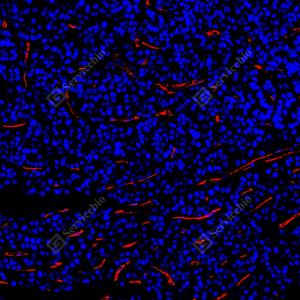

| IF检测TMEM16A/DOG1蛋白(货号 GB15920)(红色). 样品: 人结肠, 4%多聚甲醛 (货号G1101) 固定12-24小时. 抗原修复: 抗原修复仪(货号 ARI-4),Tris-EDTA抗原修复液(pH 9.0) (货号G1203), 水浴100℃, 25分钟. 封闭: 3% BSA(货号GC305010)的PBS溶液, 室温孵育30分钟. —抗: 1: 2000稀释, 4℃ 孵育过夜. 二抗: Cy3标记山羊抗兔IgG (H+L) (货号GB21303), 1: 300稀释, 室温孵育1小时. |